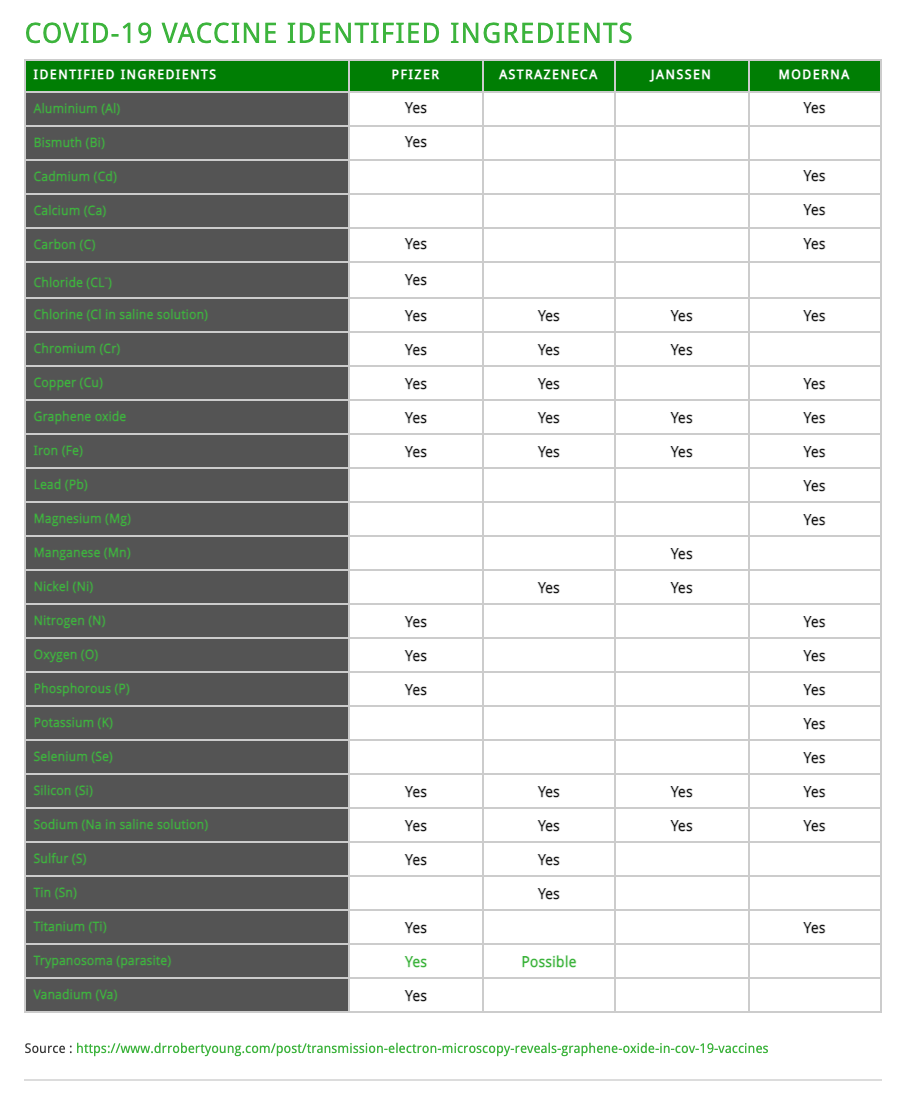

The Working Group for CoV VaXXXine Analysis states that some of the toxic elements found inside the AstraZeneca, Pfizer, and Moderna vaXXXine vials were not listed in the ingredient lists from the manufacturers. The following metallic elements were found in the vaXXXines:

From Published Research: Hikari Omni Media Publications, February 5th, 2021, “Scanning & Transmission Electron Microscopy Reveals Graphene & Parasites in CoV-19 Vaccines”, R.O. Young.

Abstract: Currently there are four major pharmaceutical companies who manufacture a SARS-CoV-2 now called SARS-CoV-19 vaccine. These manufactures and their vaccine are Pfizer–BioNTech mRNA Vaccine, the Moderna-Lonza mRNA-1273 Vaccine, the Serum Institute Oxford Astrazeneca Vaccine and the Janssen COVID -19 Vaccine, manufactured by Janssen Biotech Inc., a Janssen Pharmaceutical Company of Johnson & Johnson, a recombinant, replication-incompetent adenovirus type 26 expressing the SARS-CoV-2 spike protein.

The intended purpose of these vaccines are to provide immunity from the so-called infectious novel coronavirus or SARS-CoV – 2 virus now called the SARS-CoV – 19. These four pharmaceutical companies have not provided complete FDA disclosure on their vaccine box, insert fact sheet or label for many of the major and/or minor ingredients contained within these so-called vaccines. The purpose of this research article is to identify those specific major and minor ingredients contained in the Pfizer VaXXXine, the Moderna VaXXXine, the Astrazeneca VaXXXine and the Janssen VaXXXine using various scientific anatomical, physiological and functional testing for each SARS-COV-2-19 vaccine.

As a human right, governed under World Law by the Nuremberg Code of 1947, the vaccine specific ingredient information is critical, required and necessary to know so that any human from any country in the World can make an informed decision whether or not to consent to the SAR-CoV-2-10-19 inoculation. We have conducted the scientific testing on each vaccine and have identified several ingredients or adjuvants that have not been disclosed which are contained in these four SARS-CoV – 2 -19 vaccines.